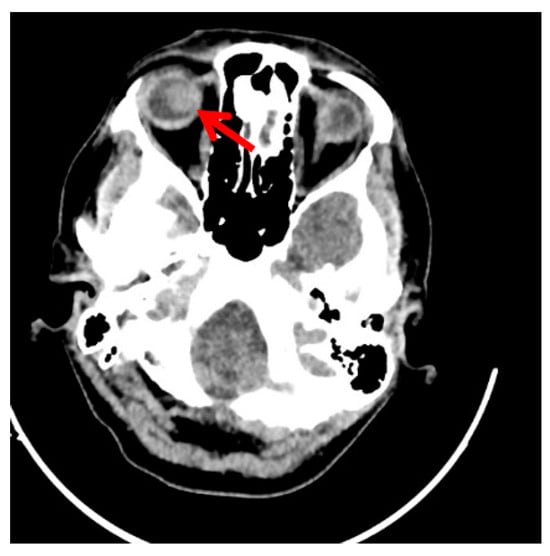

Clinical Scenario